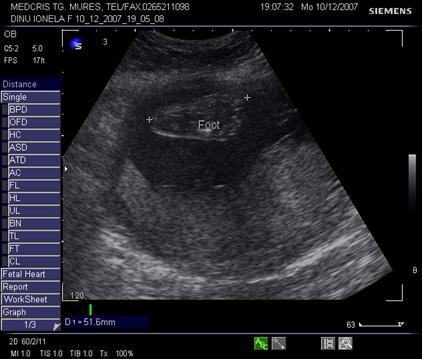

Femurul reprezinta o tinta de explorare, in special pentru biometrie, iar tibia si fibula trebuie evidentiate la ambele gambe. Ambele femure vor fi simetrice si egale. Centrii de osificare femural distal si proximal tibial apar la cca 32 - 33 saptamani, respectiv la 36 - 37 saptamani.